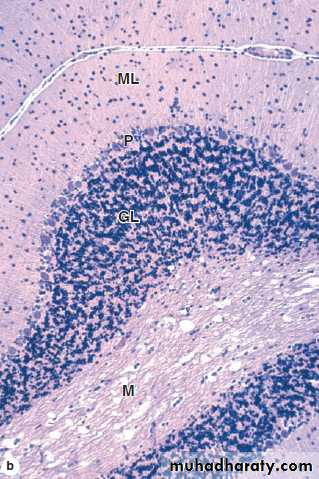

Cerebellum

Purkinje Cells